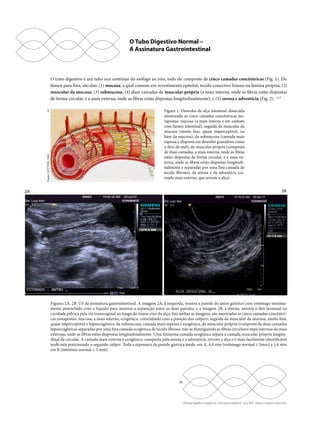

Figuras 3E, 3F. US de antro gástrico, piloro e bulbo duodenal normais. A porção do antro (3E, à esquerda), mais plana (setas retas maiores),

está em contato com a cabeça do pâncreas posteriormente e conecta-se diretamente ao duodeno, que exibe sua bolha na topografia do bulbo

(seta curva), e, entre ambos, está o piloro (setas retas menores). Na outra imagem (3F, à direita), um estreitamento é visualizado na saída do

estômago, na projeção do piloro (setas).

Figuras 3G, 3H. US de estômago normal. As dobras do corpo e fundo gástrico não são habitualmente identificáveis, mas podem ser vistas

em estômago (setas) distendido por pequena quantidade de líquido na imagem (3G, à esquerda) ou muito colabado pelo jejum prolongado

e com as dobras acentuadas pelo edema (setas) na outra imagem (3H, à direita).